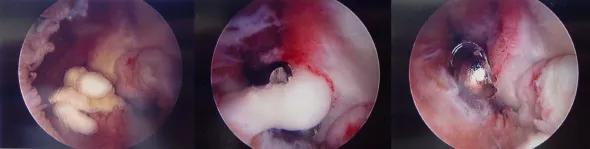

Figure 3. Arthroscopic view of an elbow with abundant soft tissue adhesions (left). Arthroscopic lysis of adhesions (middle) and debridement (right).